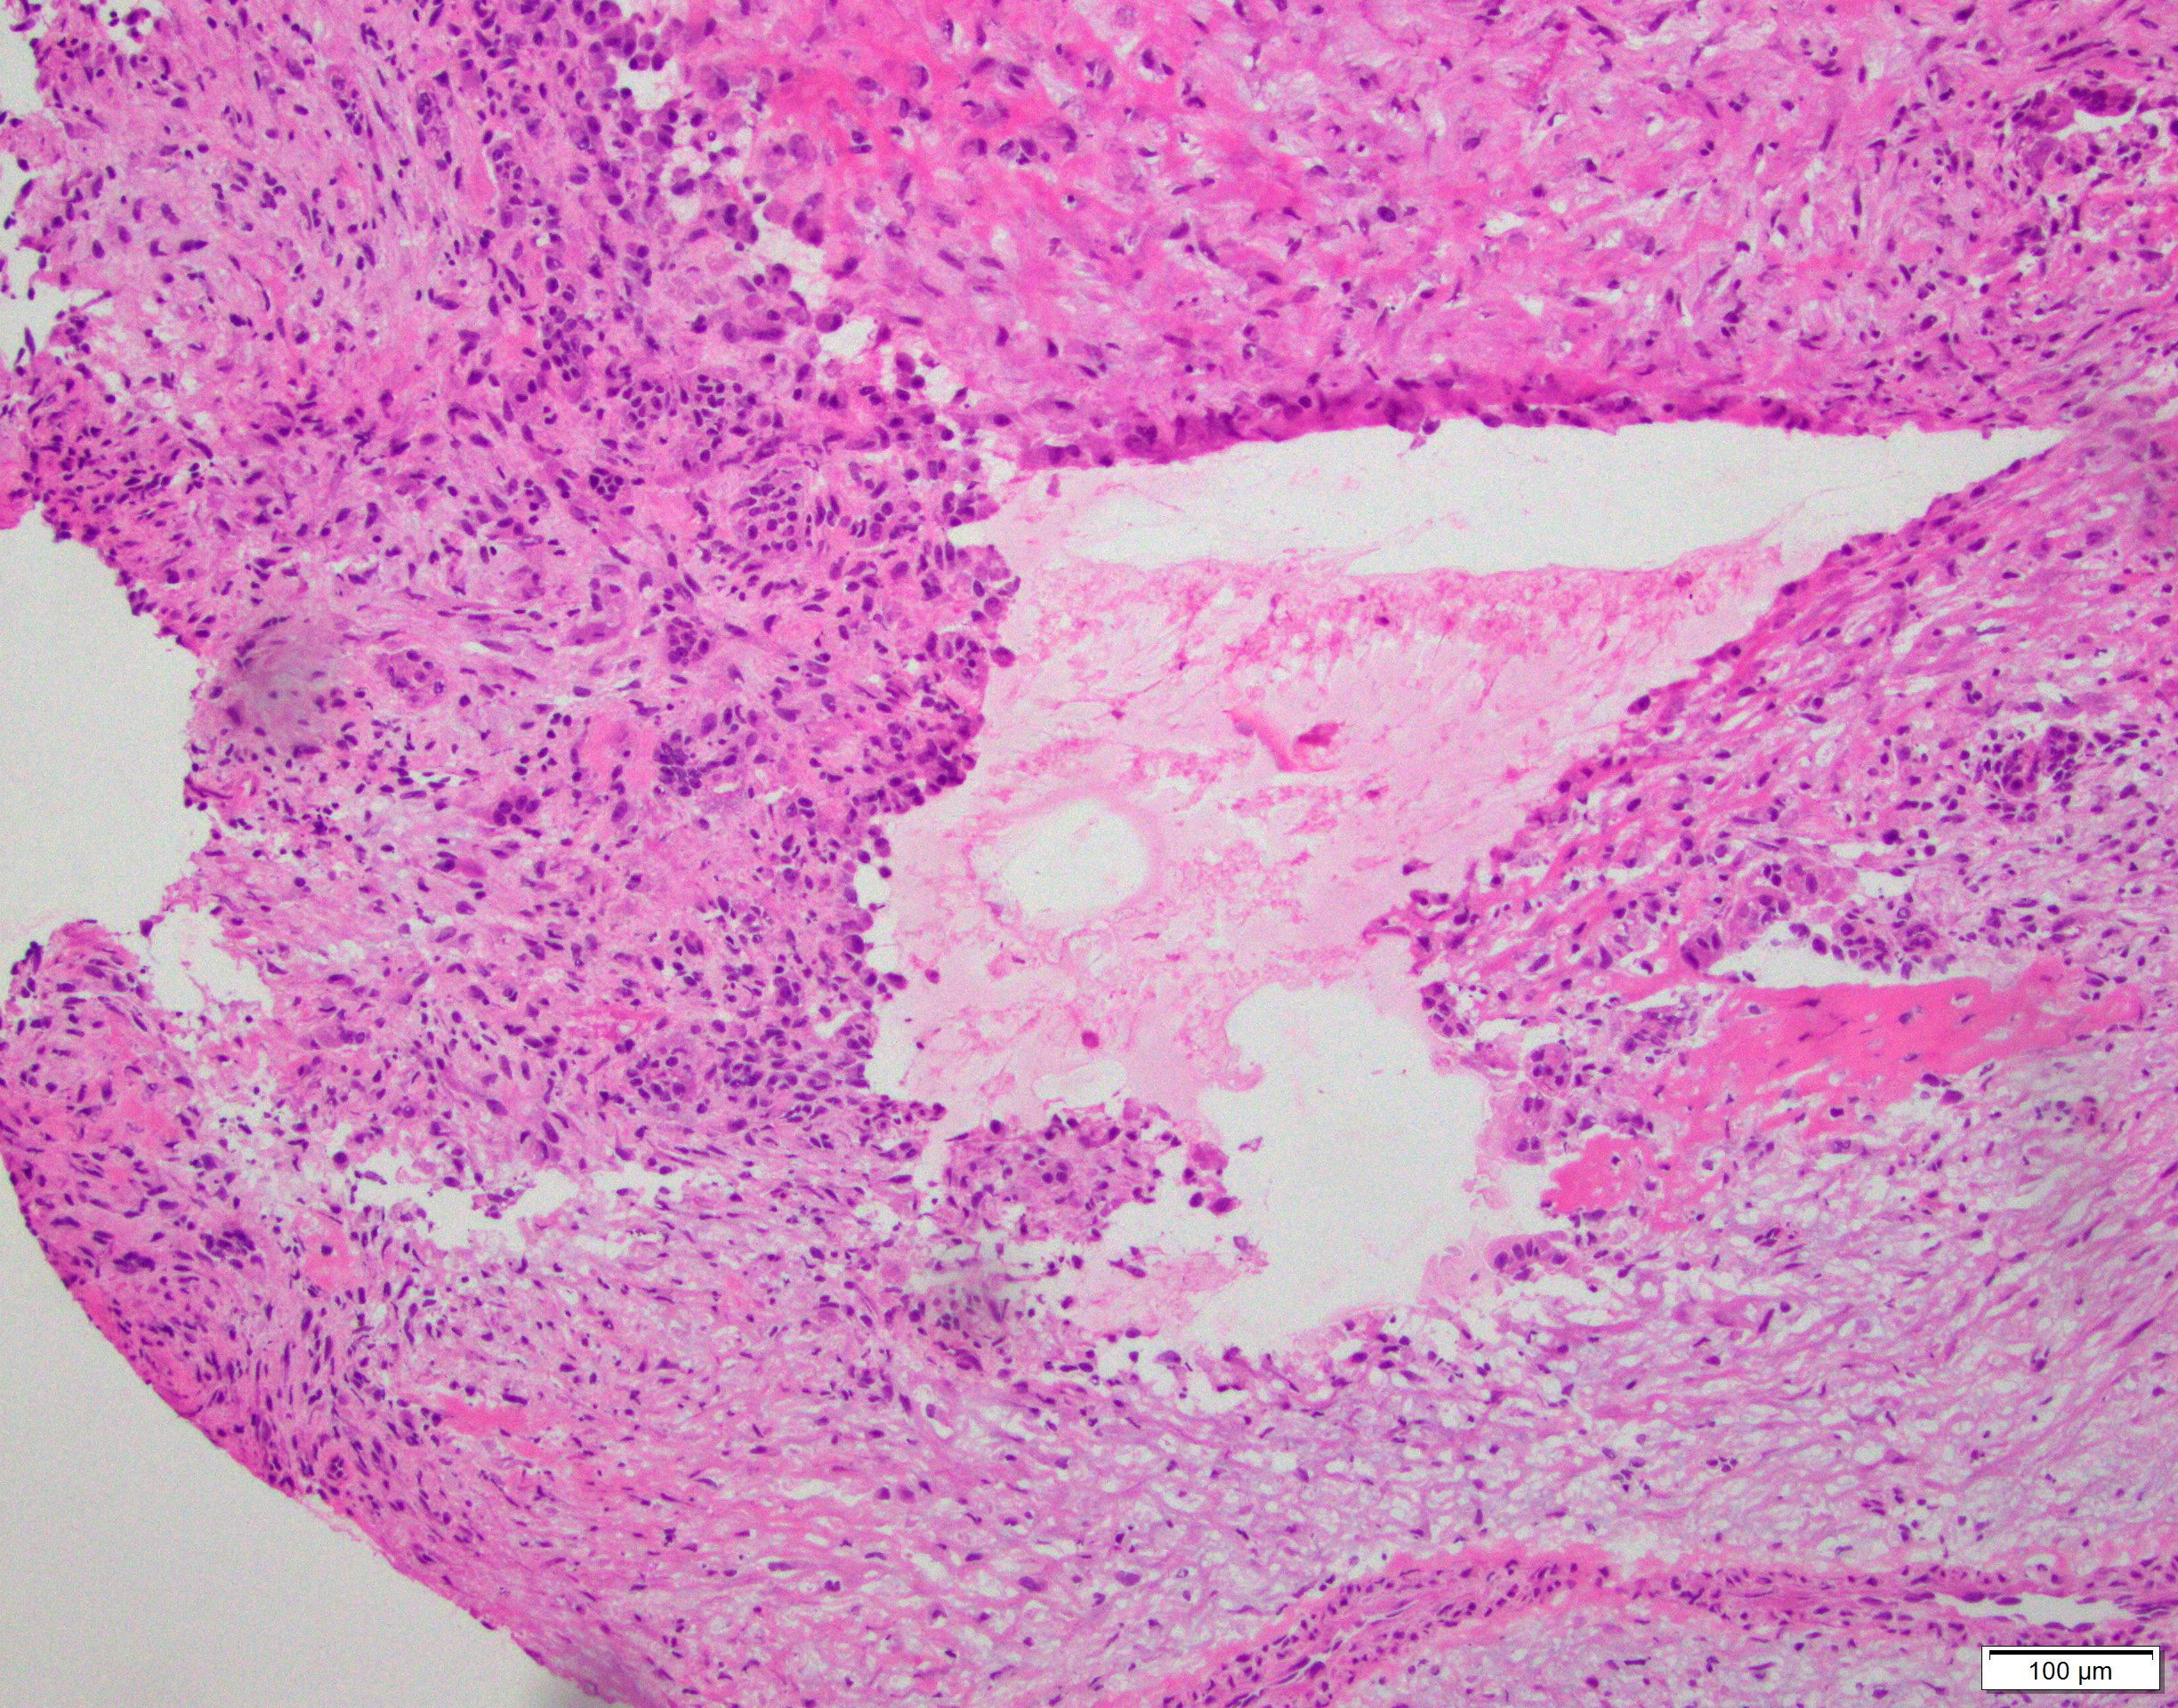

Microscopic (histologic) description

- Multiloculated cystic lesion

- Blood filled cystic spaces separated by cellular septa containing fibroblasts, giant cells and woven bone

- Calcified, basophilic material (blue reticulated chondroid-like material)

- Necrosis not common but mitotic activity is easily identified

- No cytologic atypia (Am J Clin Pathol 2015;143:823)

- Numerous giant cells in connective tissue that line large sinusoidal spaces

Microscopic (histologic) images

Contributed by Elham Nasri, M.D. and Kelly Magliocca, D.D.S., M.P.H.